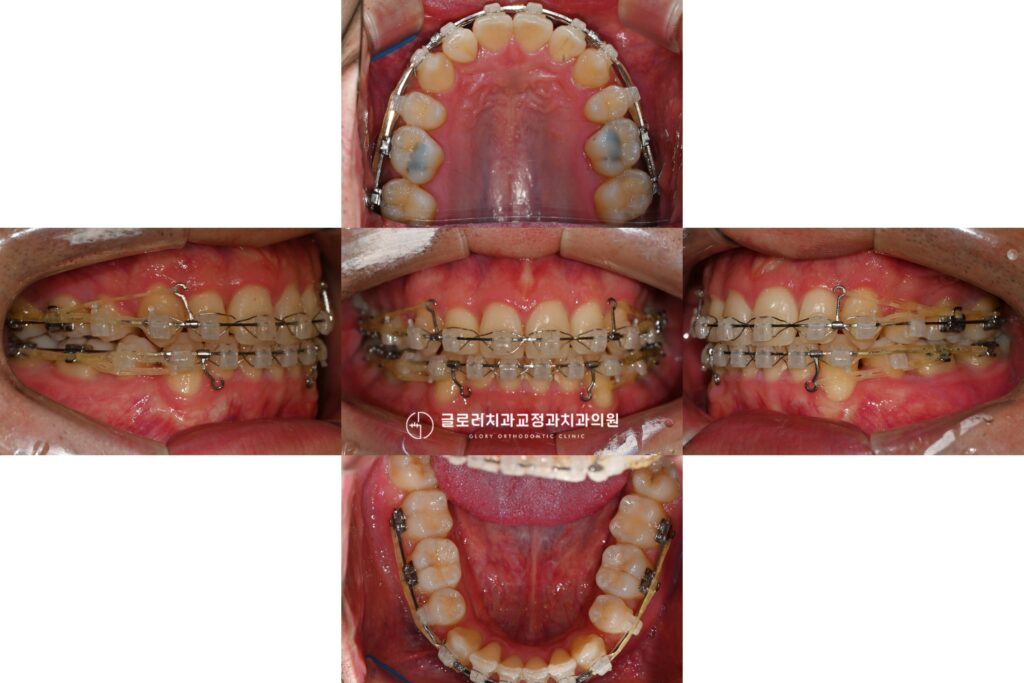

중랑구 교정치과 앞니가 삐뚤고 입이 나와보인다면? 발치교정을 통한 골격성 2급부정교합 개선 가능합니다.

안녕하세요, 교정과 전문의 김정은입니다. 앞니는 단순히 음식을 자르는 기능을 넘어 첫인상을 결정짓는 중요한 심미요소를 담당하는 부위입니다. 특히나 웃을때 제일 먼저…